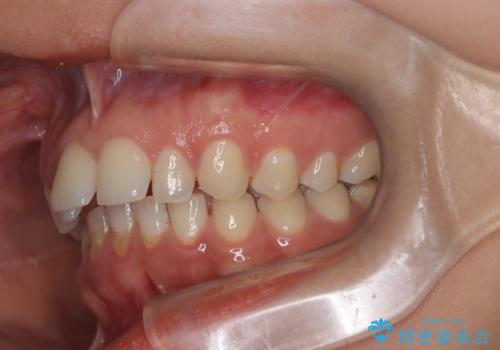

上顎前突を非抜歯で改善

- 患者様は、前歯が出ている状態(上顎前突)と隙間を閉じたいというご希望で来院されました。診断の結果、骨格性の上顎前突が確認されたため、理想的には外科矯正が必要であることを説明しましたが、患者様の「非抜歯でできる範囲で治療を進めたい」という希望を尊重し、矯正治療計画を立てました。治療目標は、前歯の突出を可能な限り改善し、隙間を閉じることに重点を置きました。

本症例では、非抜歯での治療を選択したため、スペースを確保するためにIPR(歯間削合)を行い、歯列を整えました。オーバージェット(上の前歯と下の前歯の水平的なズレ)は残る結果となりましたが、見た目や機能の改善を重視し、患者様と治療計画を共有しながら進めました。治療中は、歯列全体のバランスと噛み合わせを考慮しつつ、矯正装置の適切な使用を徹底しました。当初の計画通りに治療を完了し、患者様にも満足していただけました。